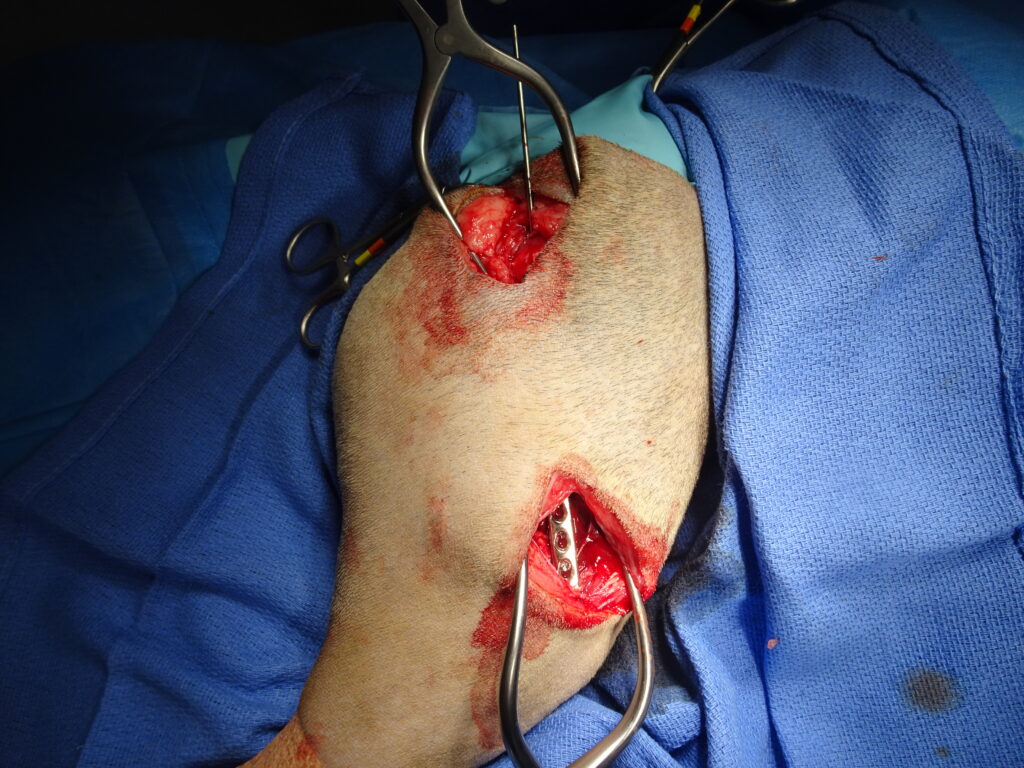

Réduction d’une luxation sacro-iliaque sur un chat par voie mini invasive. Une sis canulée est introduite de manière percutanée avec une ouverture minimale.